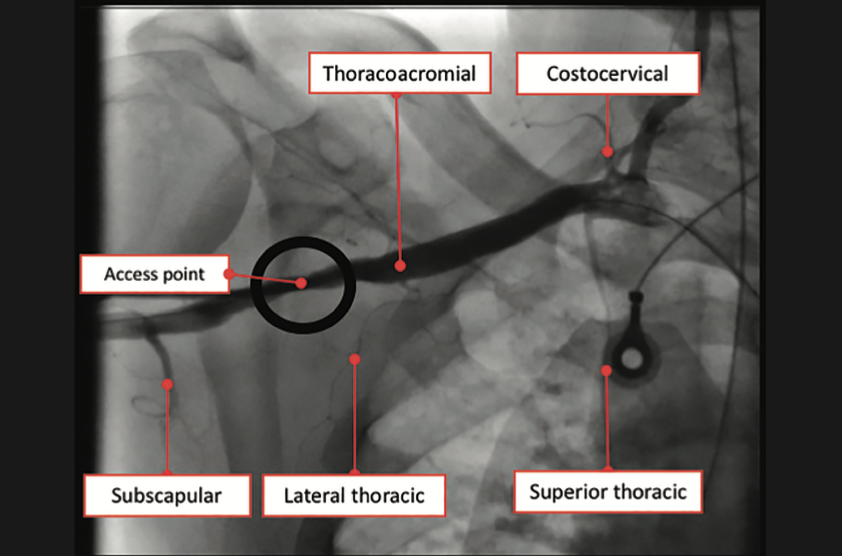

The right groin was accessed using fluoroscopic guidance. A micropuncture sheath was placed and upsized to a 7 French, 45 cm Destination sheath (Terumo) in the right groin. We accessed the right radial, but could not get good flow. Therefore, we ended up using the ulnar artery with ultrasound guidance and placed a Terumo 5/6 Slender sheath in the ulnar artery. We proceeded to access the left axillary artery. We placed a Judkins right (JR)4 catheter in the left subclavian and did a selective angiogram, documenting the location of the thoracoacromial artery and circumflex humeral (Figure 4); then using a Chiba biopsy needle (Cook), accessed the axillary artery and placed a 5-French 30 cm sheath (Cook)(Figure 5). We used the 15 cm biopsy needle to allow us a shallow angle of approach with the patient’s body habitus and to avoid “kinking” the sheath. We then switched out for the Lunderquist wire (Cook Medical), placed an 8 Fr sheath, and performed a pre-close using two Perclose devices (Abbott Vascular) (Figure 6).

Ideally, the axillary artery should be accessed in the second portion, which runs behind the pectoralis minor muscle. This is clinically important, since it is associated with the lowest chance of causing brachial plexus injury. These landmarks are often seen using ultrasound imaging. However, our practice is to use selective angiogram of the subclavian and axillary arteries. Once the axillary artery and all branches are defined, the access point should be lateral to the thoracoacromial artery and medial to the circumflex humeral arteries (Figures 22-23). We recommend a shallow angle of approach, since the Impella sheath is prone to kinking; alternatively, a Cook 14 Fr x 13 cm sheath can be used for the Impella 2.5 or a Cook 14 Fr x 30 cm sheath for the Impella CP.

- Angiographic assessment of the axillary artery and all branches is an important step to define an access point that is lateral to the thoracoacromial artery and medial to the circumflex humeral artery (Figures 22-23).